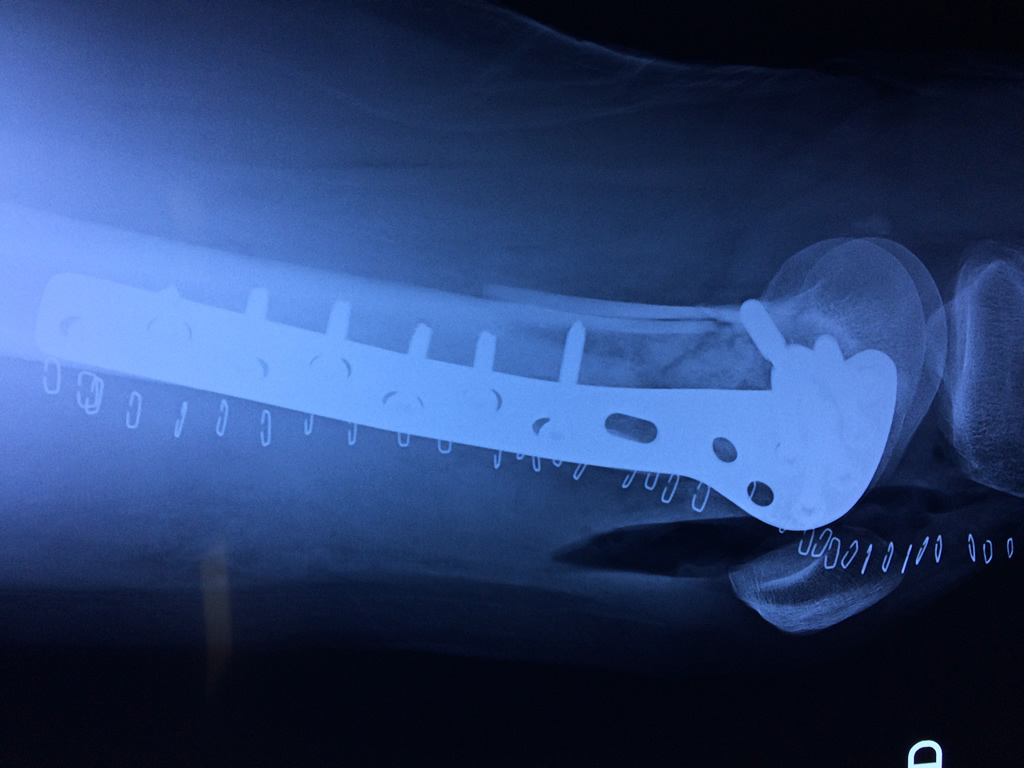

Cirugías de Húmero - Fémur

El fémur es el hueso del muslo, el segundo segmento del miembro inferior. Es el hueso más largo, fuerte y voluminoso del cuerpo humano.